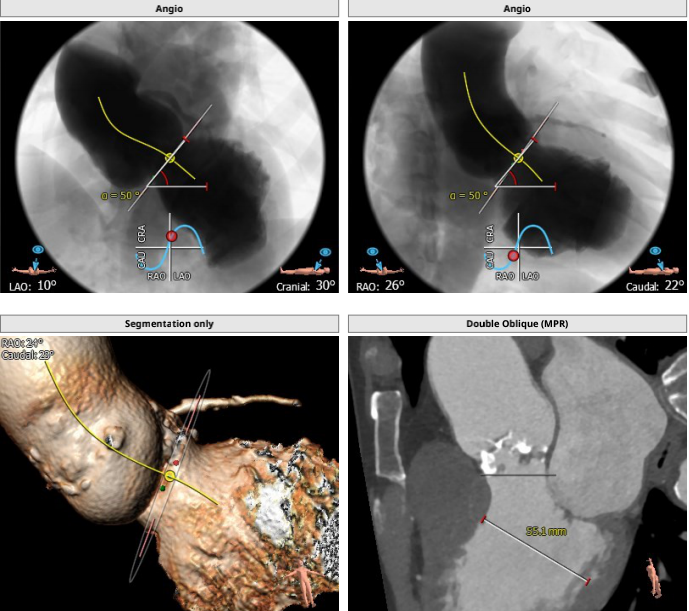

主动脉根部解剖: